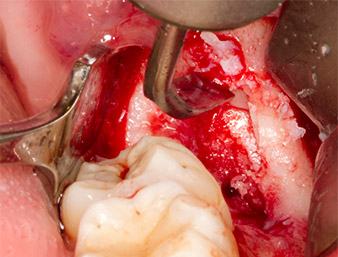

After block and local anaesthesia, the operating site was opened up and the soft tissue exposed for buccal retromolar access (Fig. 3).

sulcular incision

Fig. 3: The sulcular incision begins in mid-tooth 36 (LL6), with distal extension on the ascending ramus.

The tissue above the root remnant was not completely ossified and consisted for the most part of granulation tissue modified by inflammation (Fig. 4).

Granulation tissue

Fig. 4: Two Langenbeck retractors and a raspatorium expose the operating area. Granulation tissue of the incompletely healed first osteotomy can be seen.